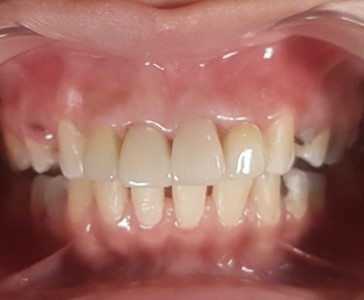

Before After

Before

After

Full E-MAX 4 crowns restoration